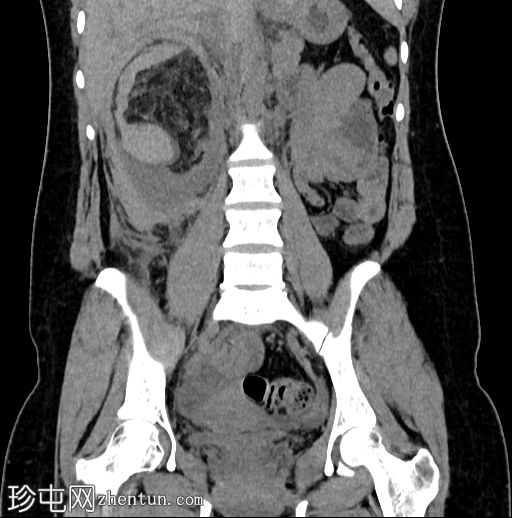

冠状位增强扫描(门静脉期)

4.jpg

右肾周间隙可见高密度影(HU=65),经右侧结肠旁沟延伸至肾盂。

右肾上极区可见一较大、边界清晰、以脂肪密度为主、伴有实性强化成分的病灶,延伸至肾盂。

该病灶延伸至肾盂区域并推移肾盏;但未见侵犯或肾积水。

符合血管平滑肌脂肪瘤破裂的特征。